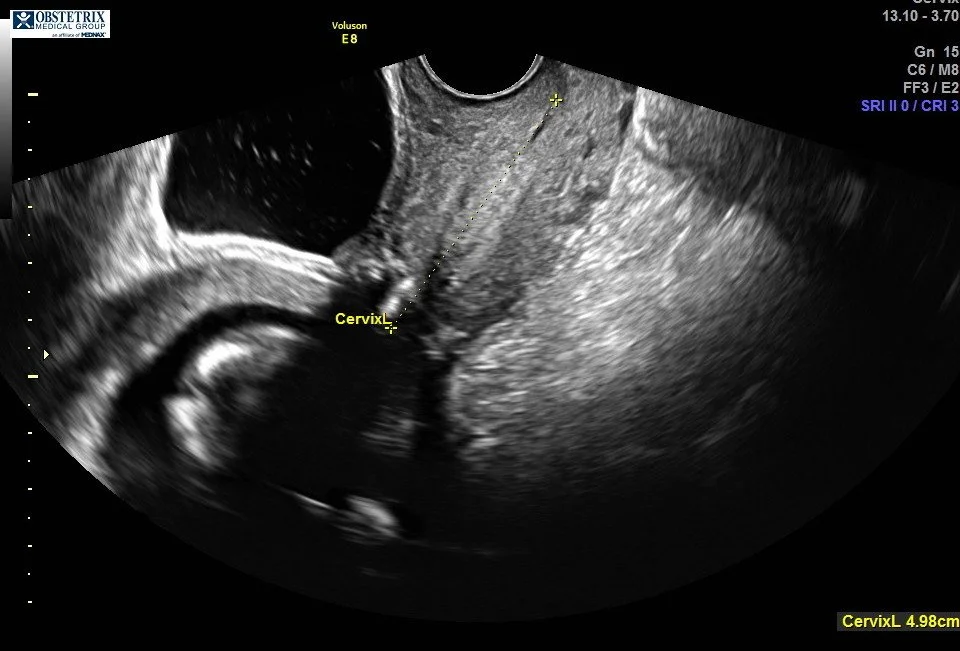

Cervical Length & TAC Update

Given my pregnancy history and my incompetent cervix, I will continue to have cervical length checks every two weeksuntil about 26–28 weeks.

At my recent 16-week cervical check, my cervix measured almost 5 cm long, which is amazing news. We were also able to see all three TAC bands placed by Dr. Haney.

(Photos below show the three TAC bands.)